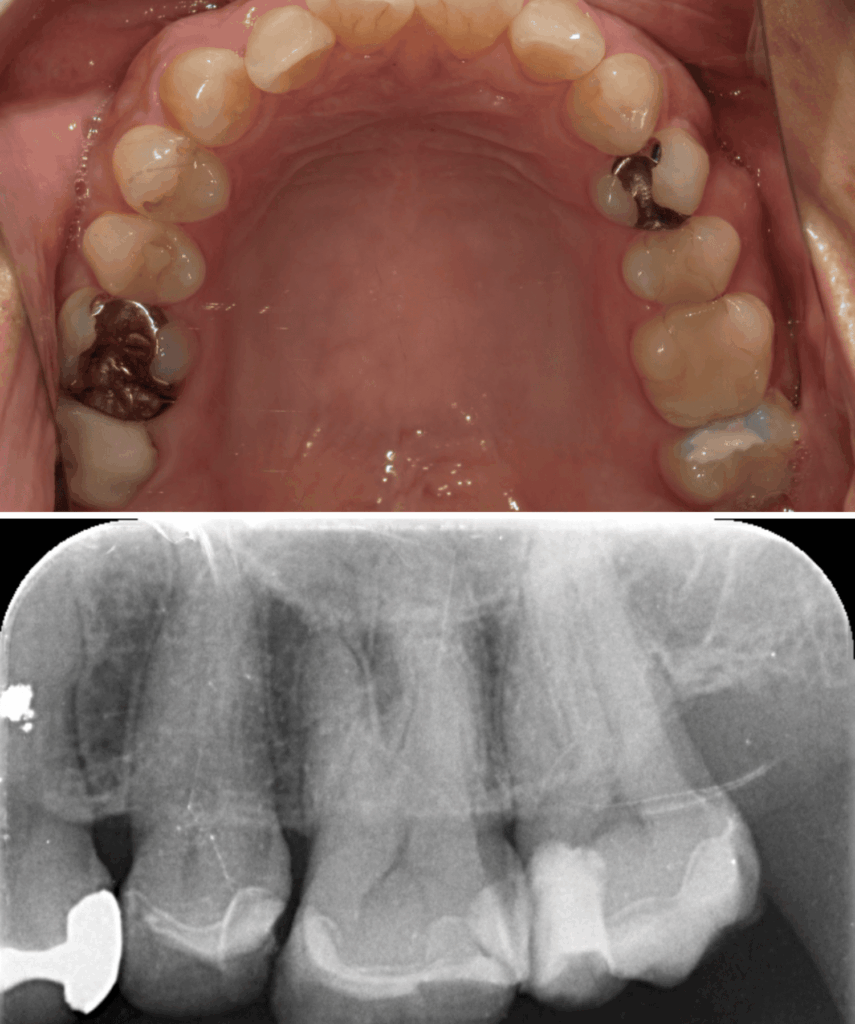

歯と歯の間のう蝕の為肉眼では分かりにくく、気づいた時には歯髄に近接し、保険治療では抜髄(神経を除くこと)になってしまうケースが多い。そのため処置前に、十分な精査と、患者さんが神経を残したいという希望の有無をしっかり相談・説明することが重要と考えています。

歯髄を温存し症状が出ないか1か月経過観察のためCRにて修復

| 診断 | ①右上7根尖性歯周炎 ②重度う蝕 ③左上7歯髄に近接するステージ3のう蝕 |

| 処置内容 (または主訴) | ①マイクロスコープによる根管治療 ②マイクロスコープによるう蝕除去およびセラミック修復 ③MTAを用いたマイクロスコープによる歯髄温存療法からセレック修復 |